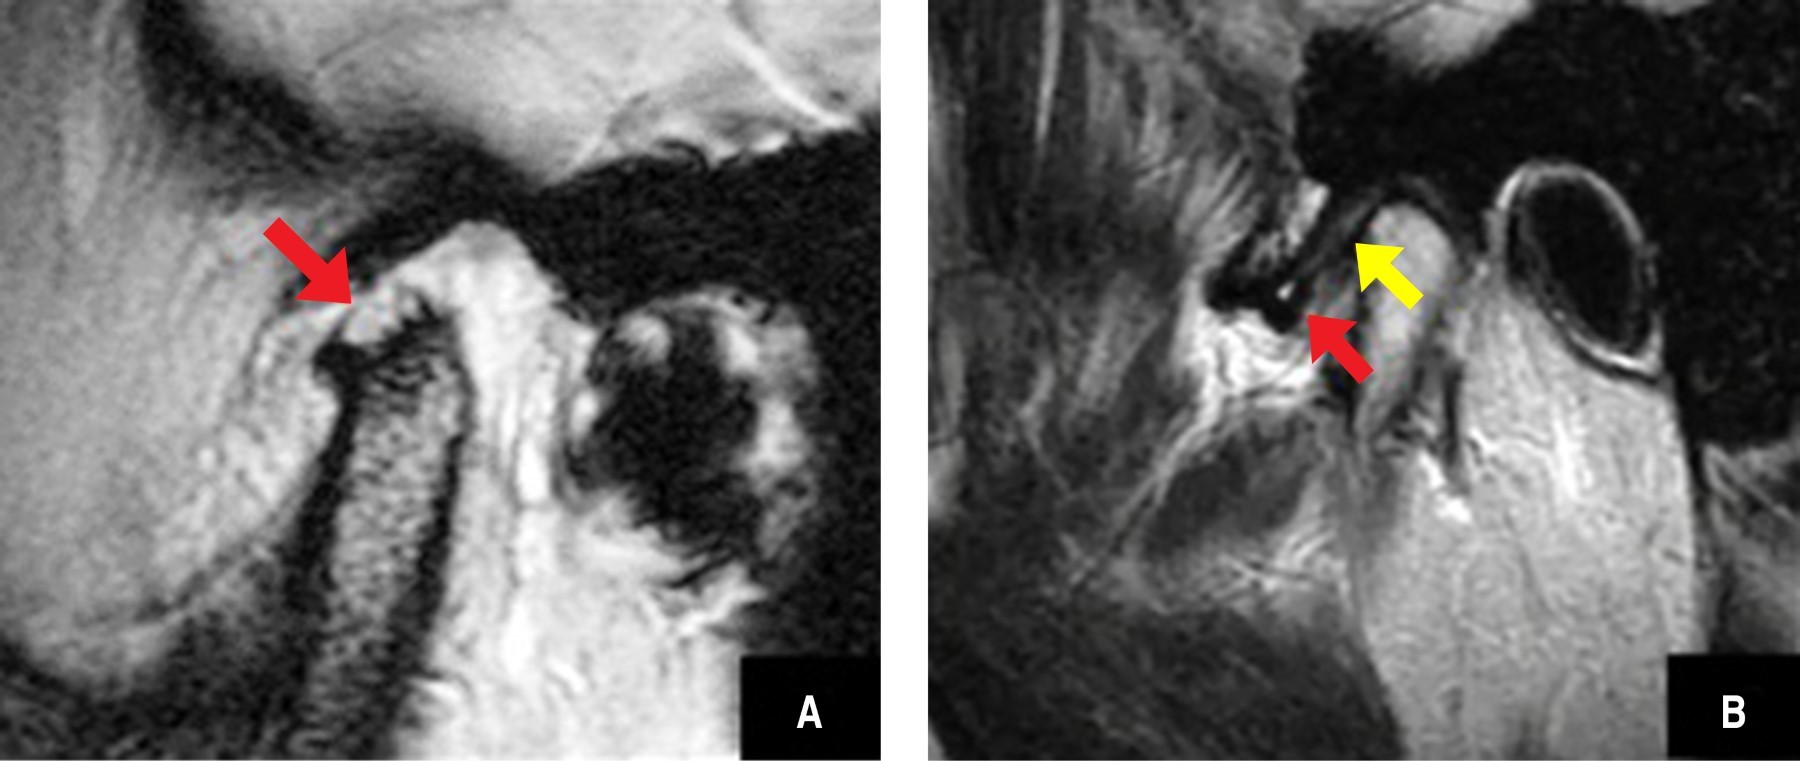

Figure 1